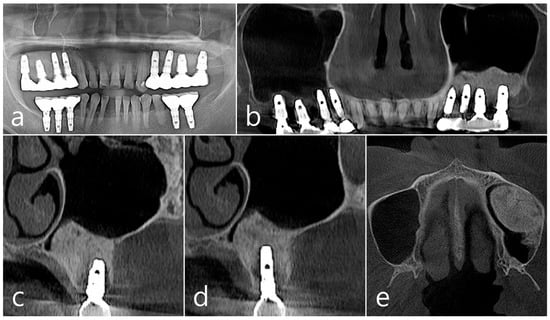

In the panoramic radiography and CBCT images taken after the prosthesis was delivered, no unusual radiographic image was observed at the bone graft site in the left maxillary sinus (Figure 3a,b). In the coronal images of the CBCT scans in #25 and #26 implants, no specific finding was found at the bone graft site of the maxillary sinus, and there was no thickening of the sinus membrane (Figure 3c,d). A well-consolidated sinus graft was observed on the axial image of CBCT (Figure 3e). The patient was checked up twice a year, and panoramic radiography and CBCT were taken 1 year after prosthesis delivery. Radiolucent images were observed around implants #25 and #26 (Figure 4a–d). A circular radiolucent image was observed in the axial image of CBCT (Figure 4e).

Figure 4. (a,b) In the panoramic radiography and CBCT images taken 1 year after prosthesis delivery, unusual radiolucent images were observed around implants #25 and #26; (c,d) Radiolucent images around #26 and #25 implants were observed. The buccal cortical plate was lost. However, the appearance of the sinus graft was well maintained, and sinus mucosal thickness was normal; (e) A circular radiolucent finding was observed in the axial image of CBCT.